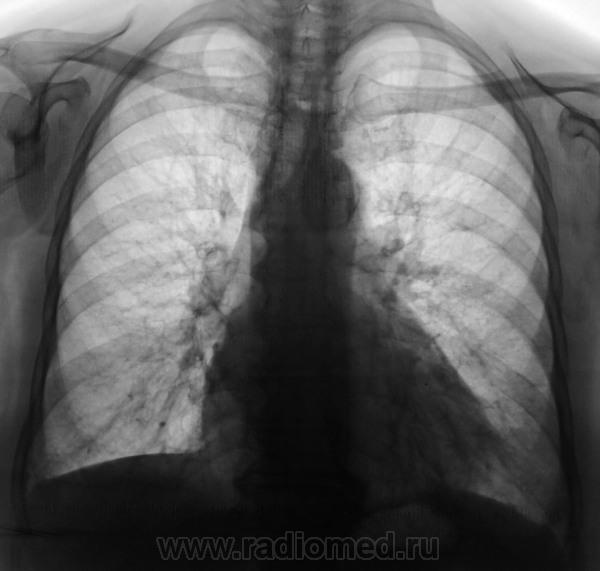

Пол пациента: Женский пол Тип патологии: Воспалительное заболевание неинфекционной природы Область исследования: Грудная клетка и верхние дыхательные пути Методы исследования: Rg Направлена на рентгенографию ОГК с подозрением на пневмонию https://radiomed.ru/sites/default/files/styles/case_slider_image/public/user/12/2.201201010021_0.jpg?itok=5JkVgdOr ID:31178 Пнд, 26/08/2013 - 17:26 #1 медсанчасть рег... Не на сайте Был на сайте: 11 лет 1 месяц назад Зарегистрирован: 11.06.2013 - 10:46 Публикации: 136 Да,можно предположить инфильтрацию S8 левого легкого,но не совсем чистые язычки. Пнд, 26/08/2013 - 17:41 #2 Kintire Не на сайте Был на сайте: 9 лет 6 месяцев назад Зарегистрирован: 25.02.2013 - 20:50 Публикации: 75 медсанчасть регион 12 wrote: Да,можно предположить инфильтрацию S8 левого легкого,но не совсем чистые язычки. +1. А слева корень не инфильтрирован? Пнд, 26/08/2013 - 20:39 #3 И.Бондаренко Не на сайте Был на сайте: 3 дня 10 часов назад Зарегистрирован: 13.09.2011 - 22:55 Публикации: 9206 Похоже, что и правая сторона задействована. Пнд, 26/08/2013 - 20:41 #4 Сергей Кузьминов Не на сайте Был на сайте: 1 год 1 неделя назад Зарегистрирован: 06.10.2012 - 15:51 Публикации: 11813 В любом случае ждать контроля,но синус передний слева уже нехорош. Втр, 27/08/2013 - 09:20 #5 Любовь С. Не на сайте Был на сайте: 9 лет 5 месяцев назад Зарегистрирован: 23.12.2010 - 01:58 Публикации: 2324 Избыточная прекардиальная клетчатка слева в диф.диагноз. "Предоставляя весь смысл и совершенство в распоряжение одного только Бога, вы избавляете себя от бездны хлопот." Джон Уитборн.

Да,можно предположить инфильтрацию S8 левого легкого,но не совсем чистые язычки.

+1. А слева корень не инфильтрирован?

Похоже, что и правая сторона задействована.

В любом случае ждать контроля,но синус передний слева уже нехорош.

Избыточная прекардиальная клетчатка слева в диф.диагноз.